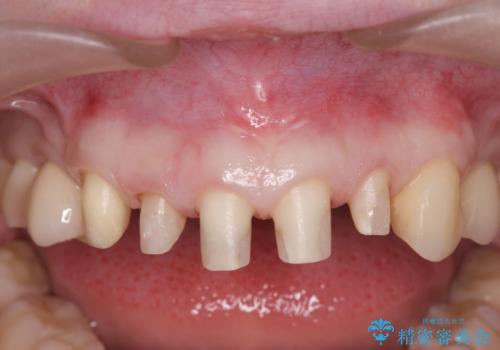

まず虫歯を拡大鏡、マイクロスコープ下で丁寧に取り除き歯肉縁下の虫歯を歯周外科により解決したのち、ジルコニアクラウン製作を行っていきます。